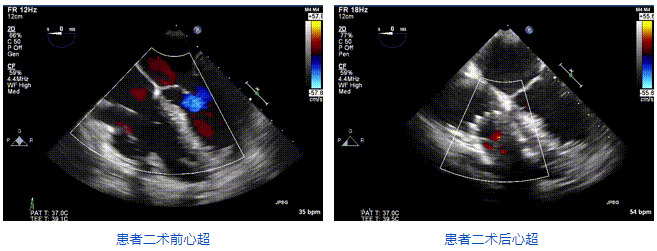

本周三例接受LuX-Valve Plus經(jīng)血管三尖瓣置換術(shù)的患者中,第一例患者為冠狀動(dòng)脈旁路移植術(shù)+Bentall+二尖瓣成形術(shù)后;第二例患者為永久起搏器植入術(shù)后,存在跨三尖瓣導(dǎo)線;第三例患者合并房顫、房缺及左心耳封堵術(shù)后。

三例患者入院后,葛均波院士團(tuán)隊(duì)周達(dá)新教授、潘文志教授、張?jiān)床┦俊㈥惿┦考靶某业呐舜湔浣淌?、李偉教授?duì)患者的情況進(jìn)行詳細(xì)評(píng)估和討論,最終決定為三例患者選擇LuX-Valve Plus40mm、50mm和50mm型號(hào)的瓣膜進(jìn)行手術(shù)治療。手術(shù)后即刻拔除氣管插管,術(shù)后患者三尖瓣反流癥狀得到顯著改善,復(fù)查心超結(jié)果顯示人工三尖瓣瓣膜支架固定穩(wěn)定,瓣葉關(guān)閉形態(tài)未見異常,未見明顯反流。